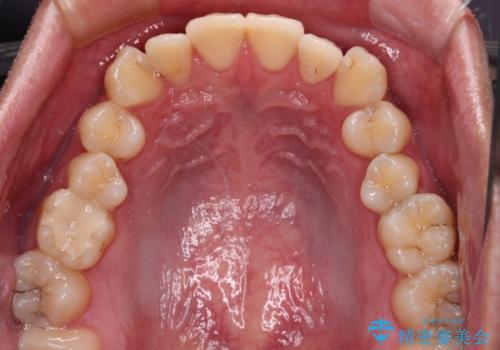

上下のデコボコを治したい インビザラインによる矯正治療

- 前歯のデコボコと突出感を気にして来院された患者様です。

極力目立たない装置を希望とのことで、インビザラインを用いて非抜歯で矯正治療を行うこととしました。

事前に親知らず4本を抜歯し、多少歯列を後方に移動できるように準備をした上で、なるべく歯と歯の間を削ることなくデコボコを解消できるように計画しました。

途中、以前大きなむし歯で処置をした歯が痛み出し、根管治療が必要となったため、根管治療とオールセラミッククラウンによる補綴治療を行い、その後にインビザラインによる仕上げの歯列移動を行い、無事に治療を終えることができました。